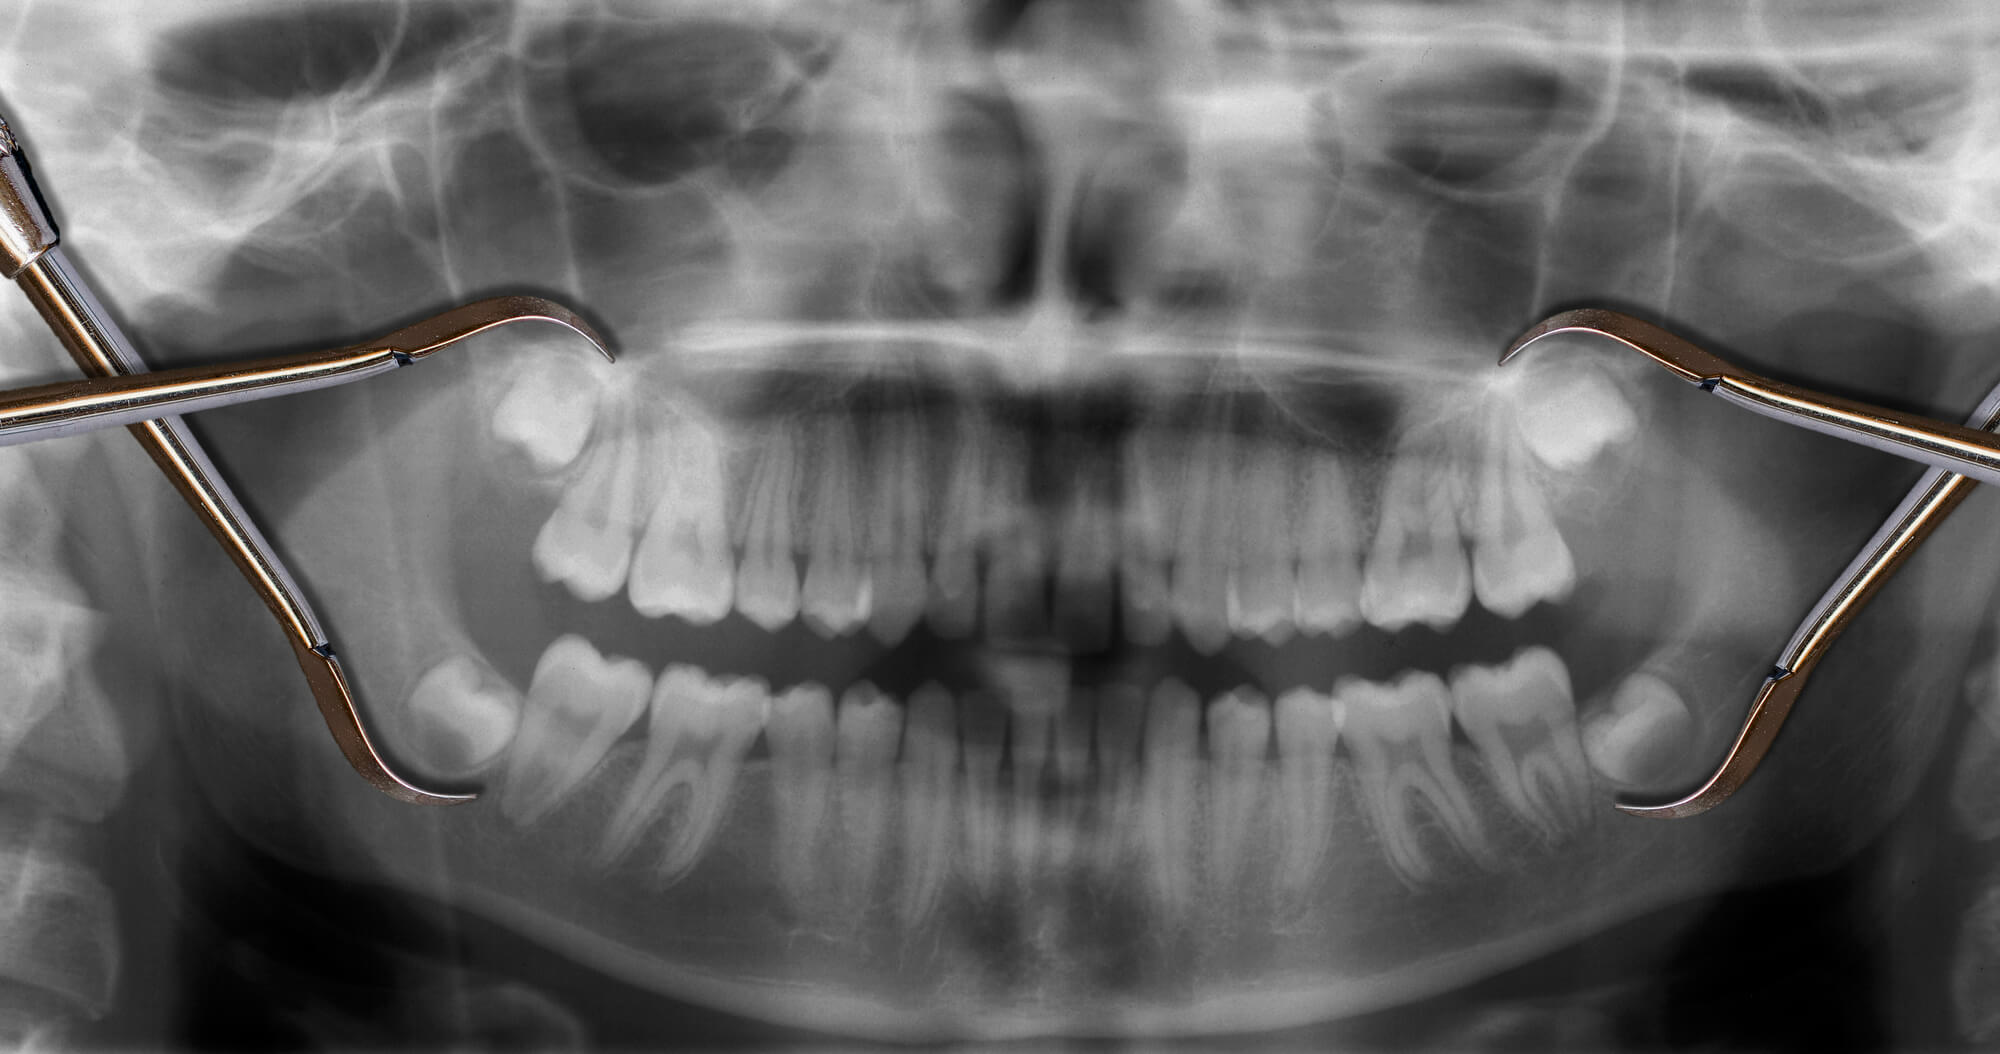

Impacted wisdom teeth are only seen when you get an x-ray for your teeth. This shows the positioning of the wisdom teeth and any unknown and hidden damages underneath the gums and the bones.

Merely checking the gums using the naked eye will not discern the impacted wisdom teeth and the hidden damage that the wisdom teeth have caused. A simple x-ray of the whole mouth is enough to help diagnose.